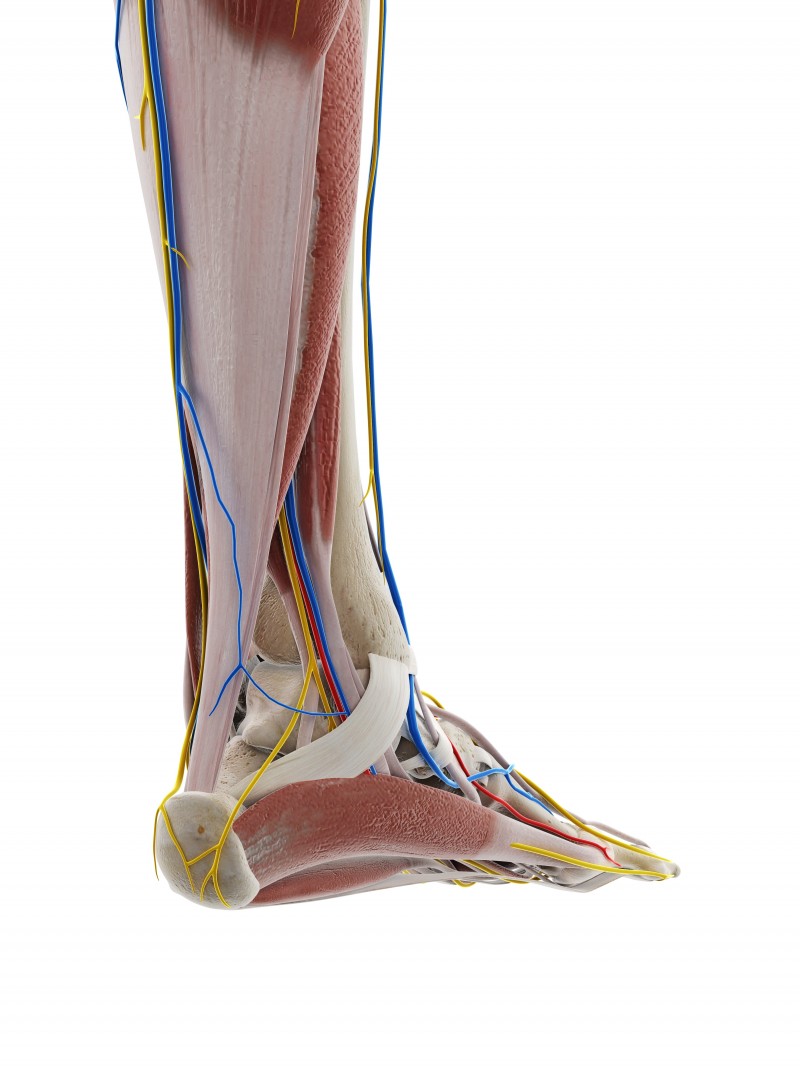

3. 신경 압박 증상

아치가 지속적으로 안쪽으로 무너지면서 굴근지대가 좁아지고, 이로 인해 신경이 압박되어 저림, 따가움, 열감, 먹먹함 등의 증상이 나타납니다. 부산 평발교정 치료는 이러한 신경 증상의 근본 원인을 해결하는 데 도움이 됩니다.